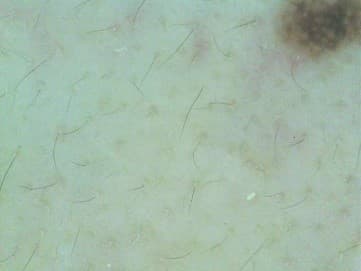

To assist diagnosis of spots, up to 5 images can be taken under the XPL light using the ChoiceTech Skin Analyzer. Our algorithm then evaluates the spots in each image and combines the individual results to provide a final spots grading. To be specific, in each image we study the color intensity of spots and classify them as light brown spots, brown spots and dark spots and visualize them as follows:

- Yellow, for light brown spots

- Orange, as brown spots

- Green, for dark spots

Table. 1 Representative images of spots detection and classification| Captured Image | Analyzed Image |

Table 3. Representative images of skin spots grade|

| Clear |  |